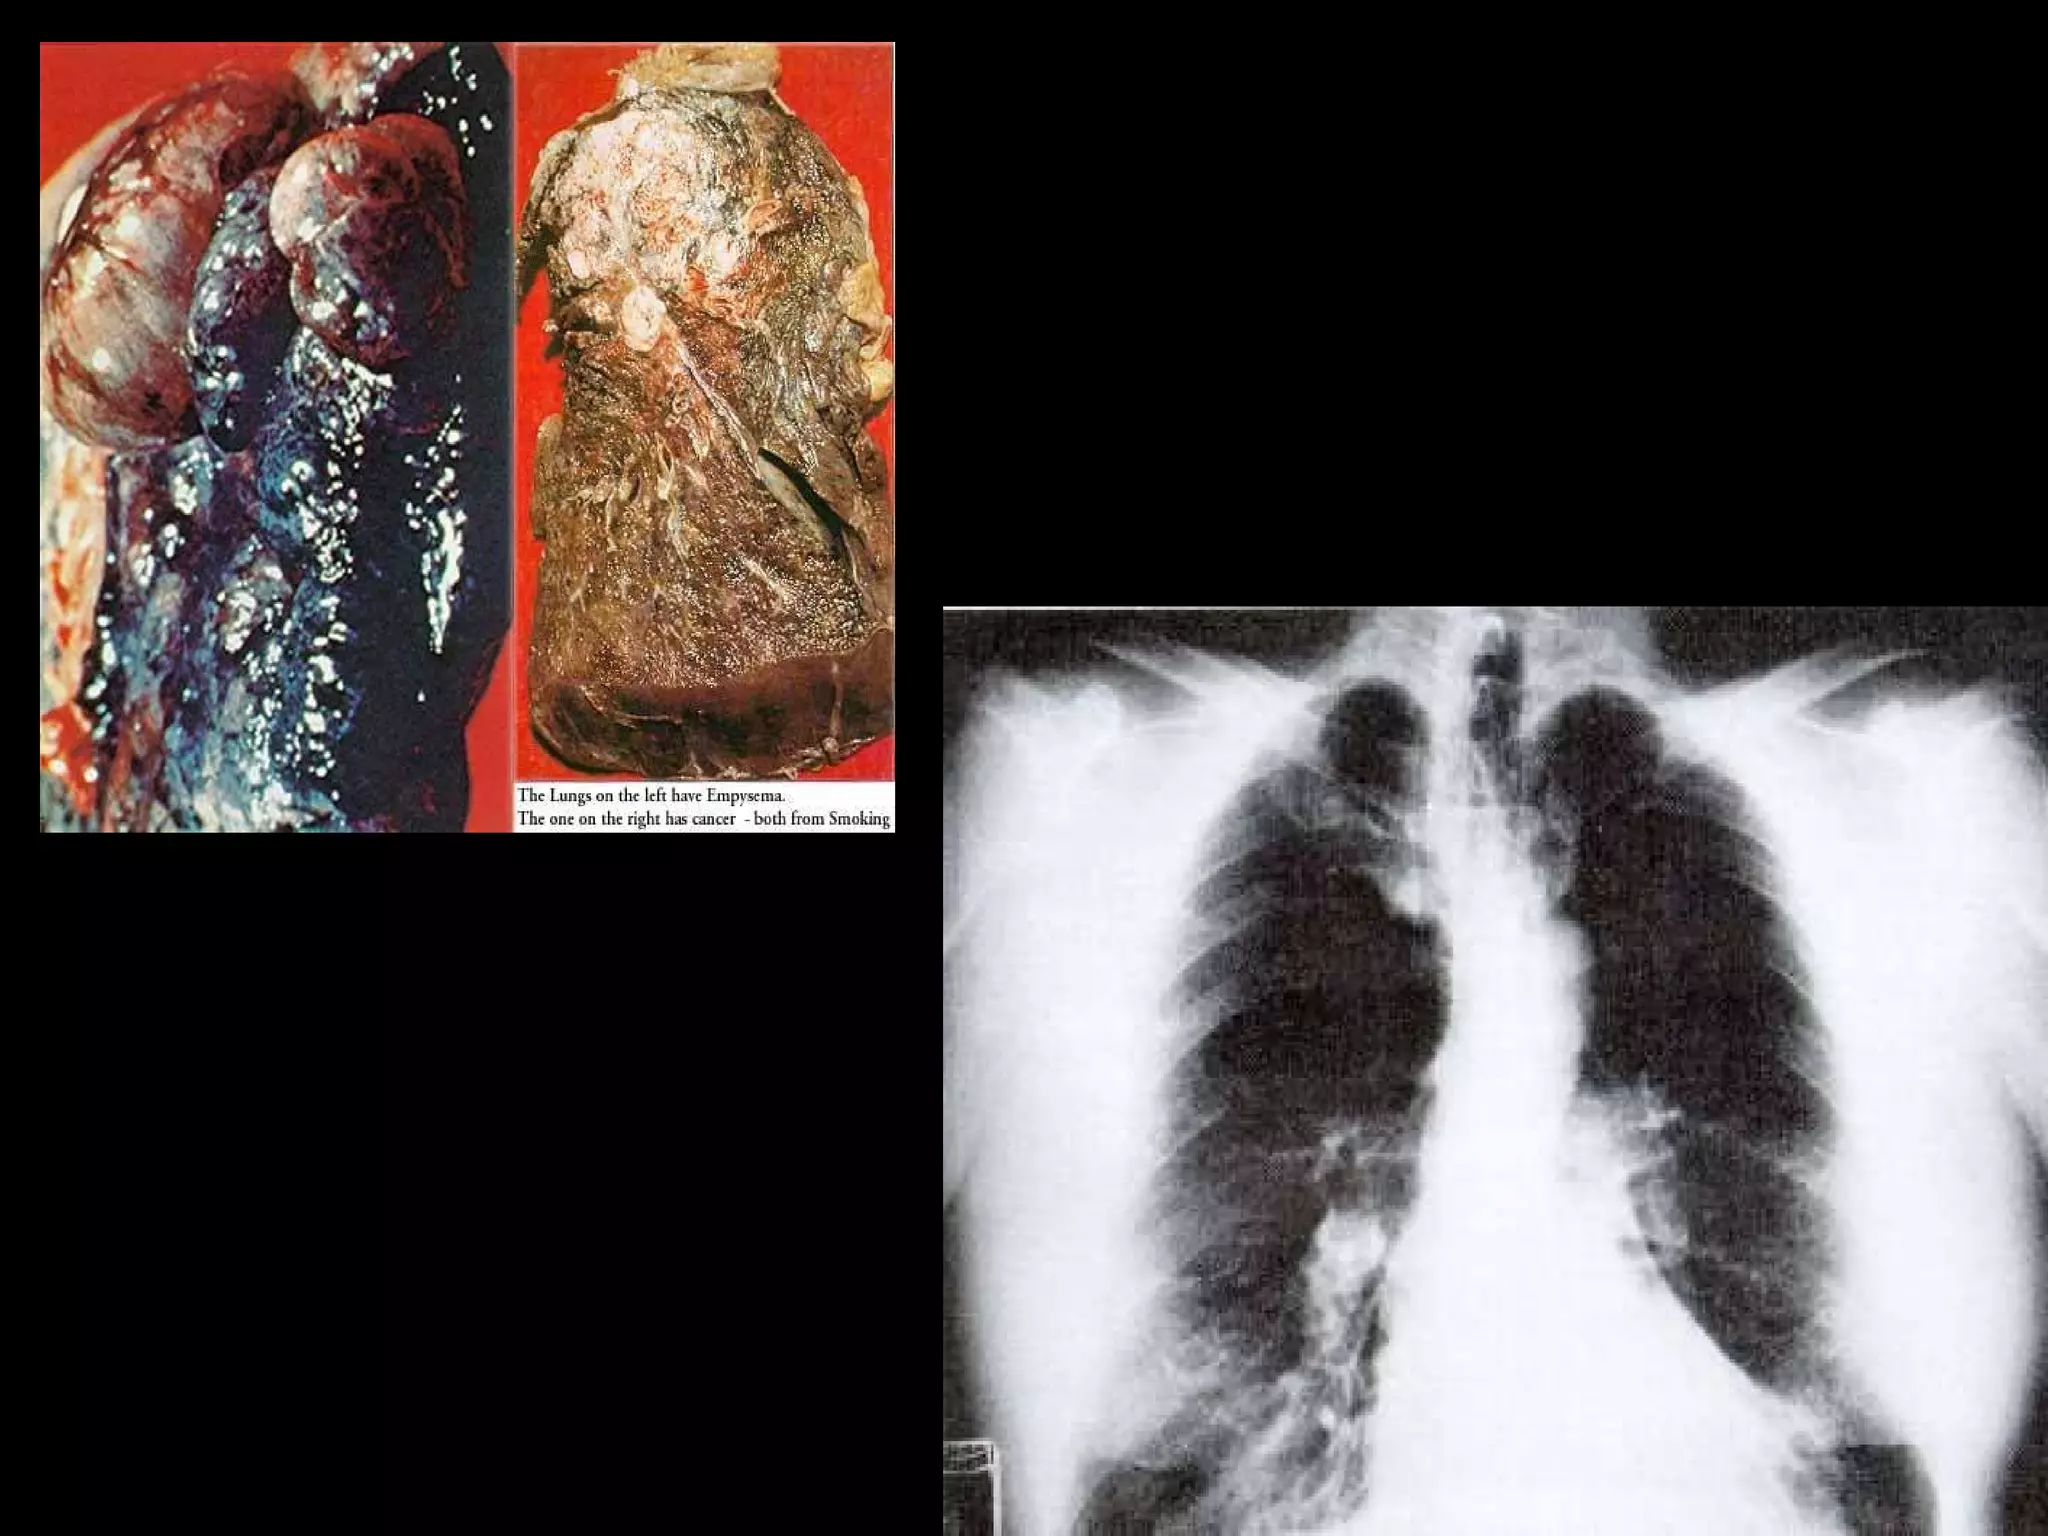

Tuberculose  Doença grave, transmitida pelo ar, que pode atingir todos os órgãos do corpo, em especial nos pulmões. O microorganismo causador da doença é o bacilo de Koch, cientificamente chamado  Mycobacterium tuberculosis .

Tuberculose Doençagrave, transmitida pelo ar, que pode atingir todos os órgãos do corpo, em especial nos pulmões. O microorganismo causador da doença é o bacilo de Koch, cientificamente chamado Mycobacterium tuberculosis .